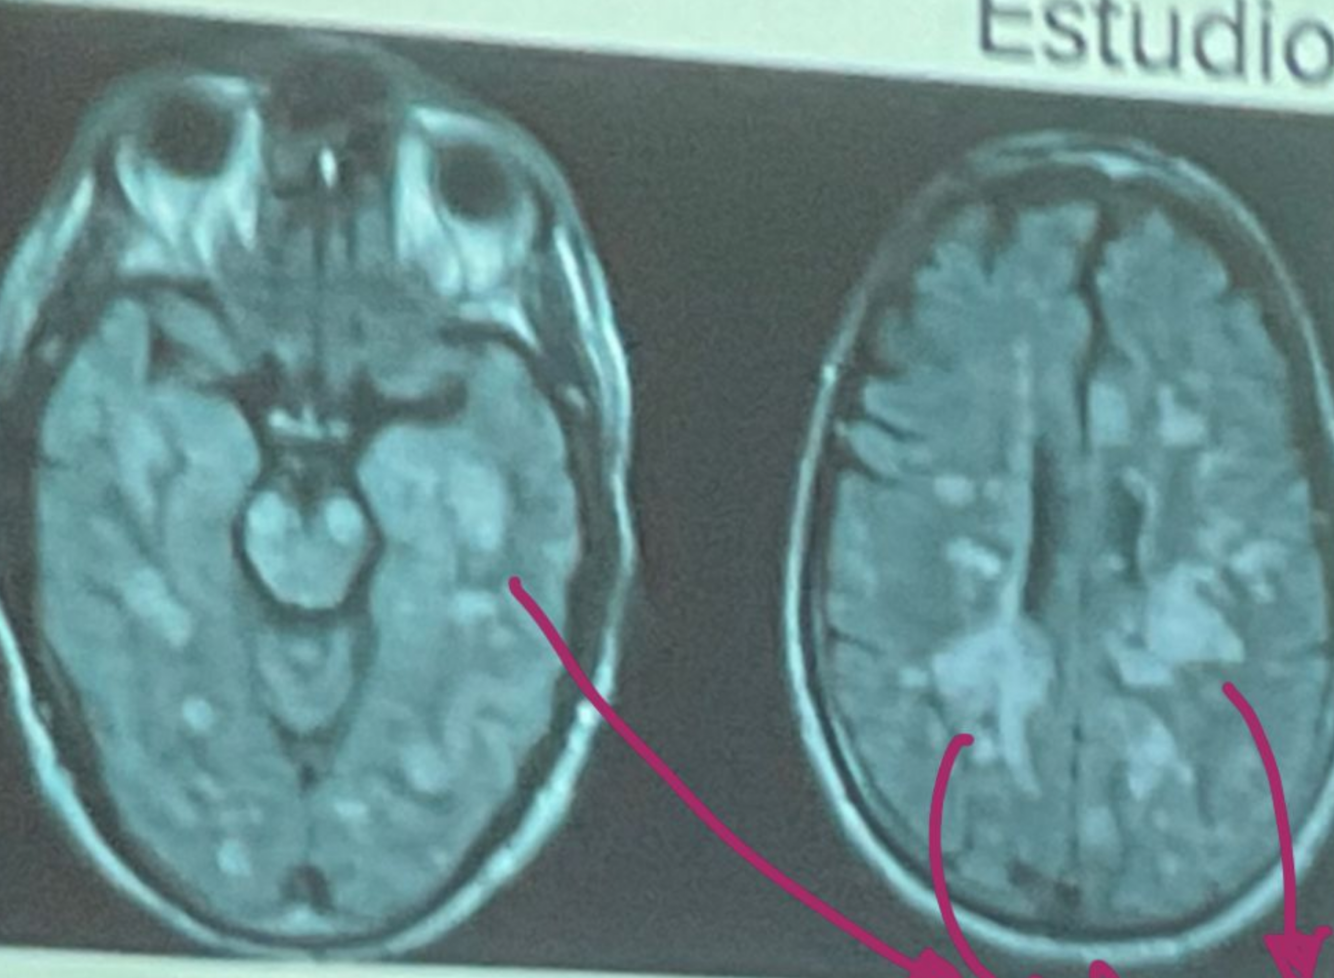

que es esto?

esclerosis multiple

Esta resonancia corresponde a ADEM/EM

EM

ADEM

En la resonancia magnetica la esclerosis multiple da estos signos:

Hiperintensidad en T2 y FLAIR

Hipointensidad en T1

Lesiones redondas y ovaladas, bordes definidos menores a 5mm